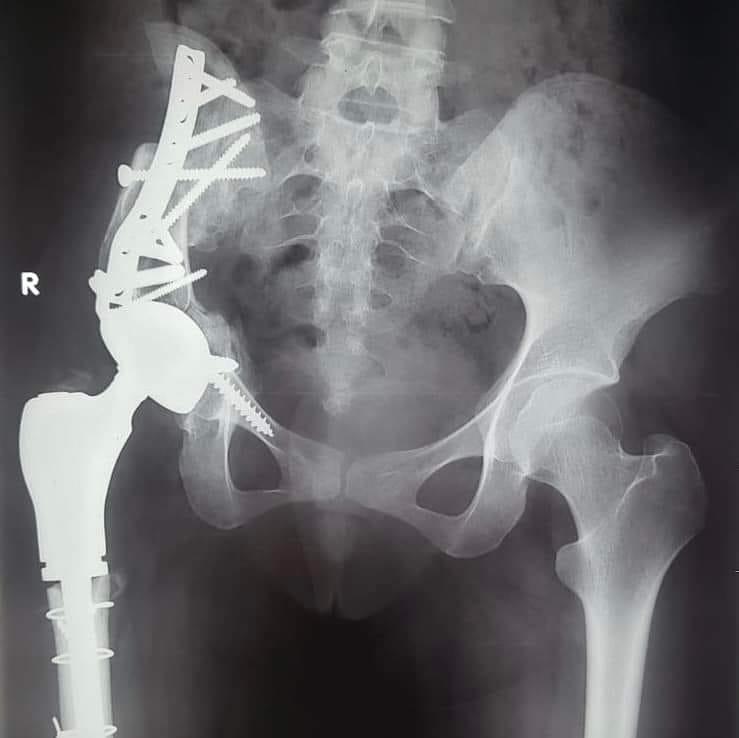

Dr Amr Al-Sayed Ali, professeur d’orthopédie et chirurgien microscopique consultant à l’Université d’Assiout, a expliqué que la patiente avait 15 ans et qu’elle souffrait d’une tumeur à l’os du mécanisme et de l’articulation pelvienne, notant que la chirurgie s’est déroulée en deux phases dans un délai de 3 mois ; éviter l’amputation, au premier stade, la tumeur a été retirée de l’os du mécanisme et la partie supérieure du fémur a été déplacée pour remplacer l’os du mécanisme.

Dr Mohamed Mahran, professeur adjoint d’orthopédie et consultant en chirurgies de remplacement des articulations artificielles à l’Université d’Assiout, a expliqué qu’après avoir effectué des examens médicaux, une articulation artificielle complète avec des spécifications spéciales pour le bassin a été installée, sans recourir à la fixation de l’articulation, et pour éviter l’amputation de ce membre.